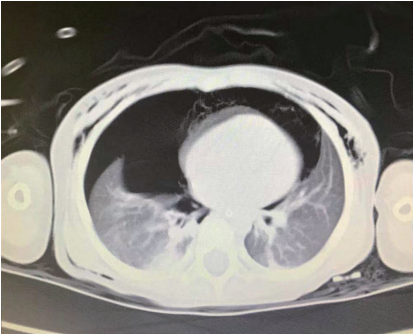

术后第4天的CT检查显示颈部、纵隔和胸壁有少量皮下气体积聚(图4A、4B)。患者于术后第7天出院,拒绝进行纤维支气管镜检查以确定病因,出院后随访中未观察到异常。

图4. CT显示颈部、纵隔和胸壁有少量皮下气肿